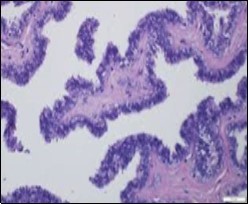

Figure 1.Ciliated cutaneous cyst lined by pseudostratified ciliated columnar epithelium and a supporting fibro-connective tissue stroma 11.

Typically, cutaneous ciliated cyst is a simple cyst which demonstrates a layering of pseudostratified ciliated columnar epithelium recapitulating conventional epithelial lining of the fallopian tube. As the cutaneous ciliated cyst demonstrates a morphological similarity to the fallopian tube lining epithelium, a Mullerian origin is indicated. Gross examination of cutaneous ciliated cyst depicts a solitary, mobile, non-tender, fluctuant, firm or soft to cystic lump with a fibrous wall and abundant amount of circumscribing adipose tissue. Cutaneous ciliated cysts are of a variable dimension. Cut surface usually displays a unilocular cyst impacted with clear, serous fluid, an attenuated smooth, greyish/ white cyst wall incorporated with incomplete septa traversing the cyst 6, 7.

Cutaneous ciliated cyst is layered with a singular layer of ciliated epithelial cells which are chiefly constituted by cuboidal to columnar epithelium, traversed by partially configured fibrous tissue septa with an admixture of randomly dispersed, intraluminal papillary projections akin to those cogitated in the fallopian tube. Superimposed epithelium is inundated with well vascularized, parallel bundles of collagen although smooth muscle is absent 7, 8.